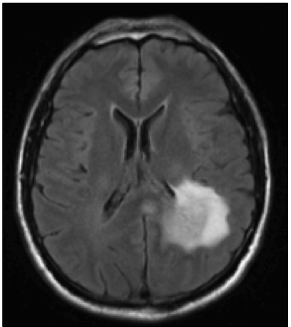

Refer to caption

Figure 1: (a) post-gadolinium T1 weighted image of a glioblastoma located in the left parietal lobe. (b) T2-FLAIR image of the same tumor, showing the surrounding peritumoral edema. (Note that the right side of the image corresponds to the left side of the brain to follow brain imaging conventions.)

The tumor growth calculations are based on MR images routinely acquired in clinical practice. The images incorporated into the simulation process are T1, T2, T2-FLAIR, and T1 post gadolinium. The T1 post gadolinium image shows the vascularized gross tumor volume, and the T2-FLAIR image shows the surrounding edematous region. For illustrative purpose, these two images are shown in figure 1 for a case discussed in detail in this paper.